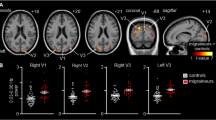

When comparing patient groups among them and with HC, during moderately painful THS (51°), we observed: i) a significantly greater BOLD-response in left lingual gyrus, inferior parietal lobe, inferior frontal gyrus (see Figs. 1 and 2) and cerebellum in patients with MwA compared to MwoA patients (Fig. 3); ii) a significantly greater BOLD-response in the cerebellum in patients with MwA compared to HC (Fig. 3); iii) a significantly greater BOLD-response in medial frontal gyrus (see Figs. 1 and 2) in patients with MwA compared to HC; iv) no other difference in BOLD response has been observed between both MwA patients group and MwoA patients group and HC.

Group-level (main effects) BOLD-response of advanced visual network (encompassing lingual gyrus, inferior parietal lobule, inferior frontal gyrus and medial frontal gyrus) in patients with MwA, MwoA and HC during THS at 51 °C. Statistical maps were obtained overlaying an inflated 3D brain surface from the ‘Colin 27’ atlas (p < 0.001 cluster-level corrected). MwA = migraine with aura; MwoA = migraine without aura; HC = healthy control)

Percent of BOLD signal change (mean ± SE) at 51 °C from left lingual gyrus, left inferior parietal lobule, left inferior frontal gyrus and left medial frontal gyrus clusters in patients with MwA compared to HC and patients with MwoA. SE = standard error; MwA = migraine with aura; HC = healthy controls; MwoA = migraine without aura.

Altogether, lingual gyrus, inferior parietal lobule, inferior frontal gyrus and medial frontal gyrus encompassing the so-called advanced visual processing (AVN) [10,11,12,13].

Talairach coordinates of significant cluster differences between groups are reported in Table 2. Mean values of percentage BOLD signal changes were extracted from following clusters: lingual gyrus (MwA: 0.12 ± 0.03; HC: 0.031 ± 0.02; MwoA: − 0.029 ± 0.02; MwA vs HC p:0.005, MwA vs MwoA p < 0.001, MwoA vs HC p:0.02), inferior parietal lobule (MwA: 0.11 ± 0.02; HC: 0.05 ± 0.03; MwoA: − 0.03 ± 0.05; MwA vs HC p:0.06, MwA vs MwoA p < 0.001, MwoA vs HC p:0.002), inferior frontal gyrus (MwA: 0.13 ± 0.03; HC: 0.06 ± 0.03; MwoA:-0.05 ± 0.02; MwA vs HC p:0.13, MwA vs MwoA p < 0.001, MwoA vs HC p:0.001), medial frontal gyrus (MwA: 0.13 ± 0.03; HC: 0.01 ± 0.02; MwoA:0.04 ± 0.02; MwA vs HC p: p < 0.001, MwA vs MwoA p:0.008, MwoA vs HC p:0.39) and cerebellum (MwA: 0.11 ± 0.02; HC: 0.03 ± 0.01; MwoA: − 0.02 ± 0.01; MwA vs HC p < 0.001, MwA vs MwoA p < 0.001, MwoA vs HC p:0.006) (see Figs. 2, 3 and 4).